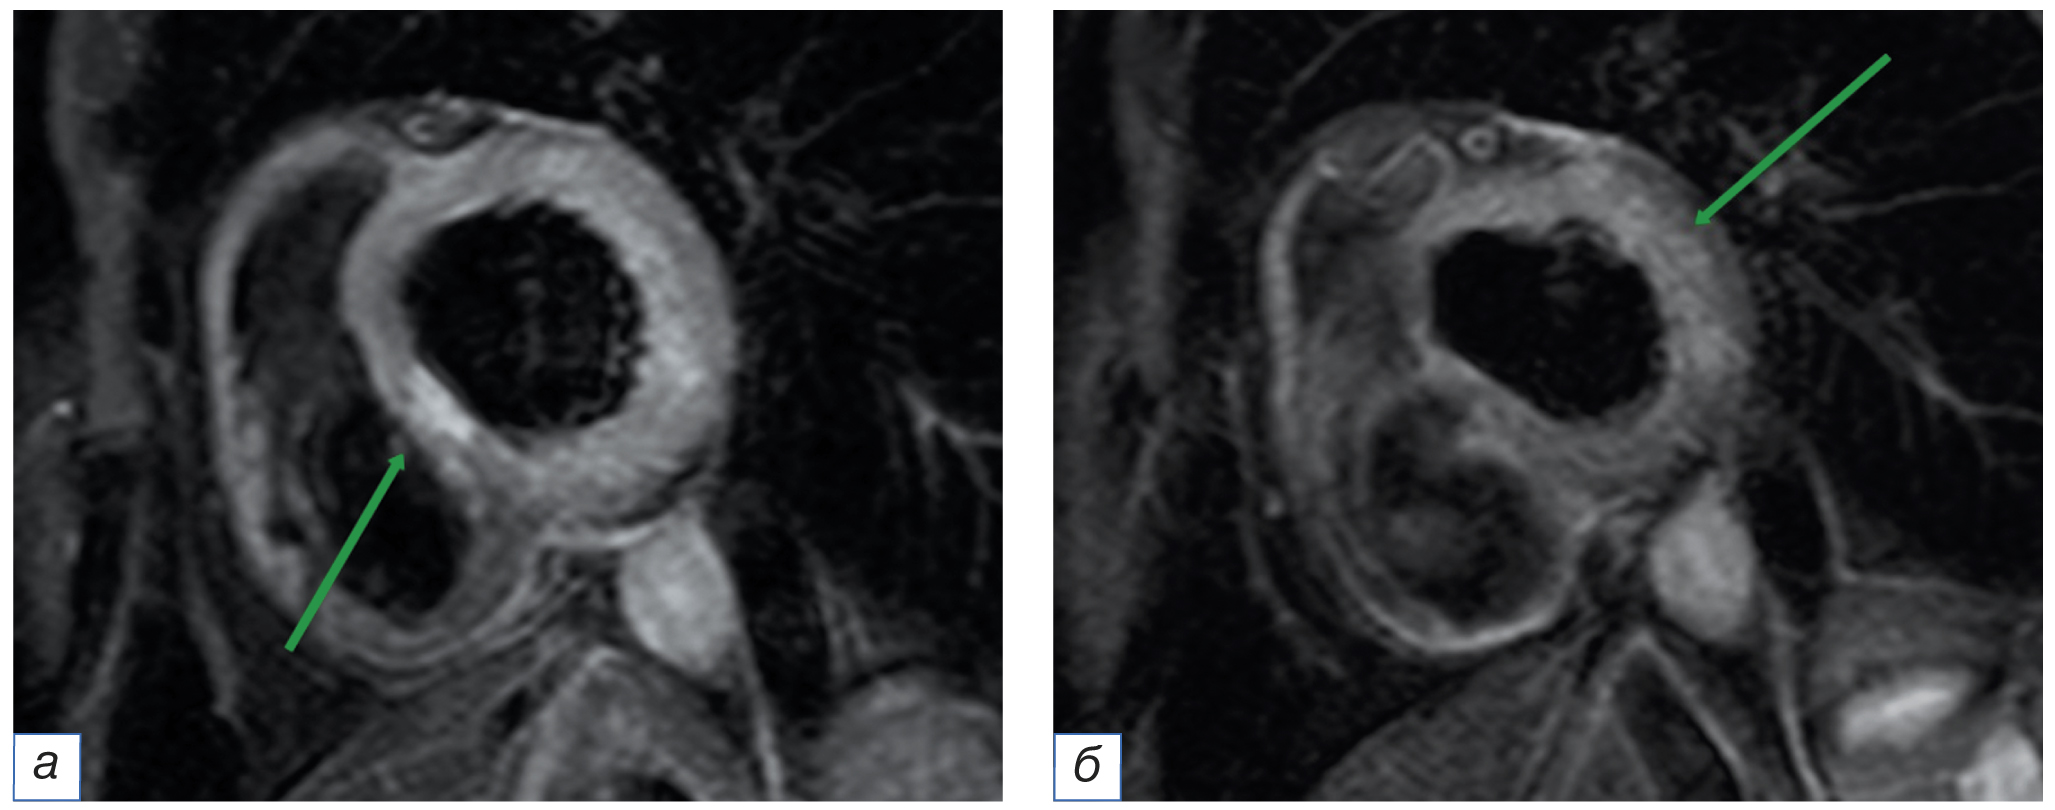

Симметричное утолщение миокарда в систолу свидетельствует о нормокинезе, т.е. нормальном сокращении стенок. В случае локальных/распространённых участков повреждения миокарда отмечается асимметричное утолщение стенок в систолу, что говорит о зонах гипокинеза, отсутствие утолщения стенок — об акинезе (рис. 2). Термин «дискинез» используют в случае снижения эластической функции (сопротивляемости давлению внутри левого желудочка) и выбухания поражённой стенки кнаружи. Зоны дискинеза наиболее часто встречаются в аневризмах левого желудочка [14–16].

Рис. 2. Магнитно-резонансная томография сердца, последовательность CineFiesta (кинорежим), изображения по короткой оси сердца: а — диастола (короткой стрелкой указана нижняя стенка левого желудочка с нормальной толщиной, длинной стрелкой — область истончения миокарда); б — систола (короткими стрелками указано утолщение во время сокращения нормального миокарда левого желудочка, длинной стрелкой — участок акинеза в поражённом миокарде).

Fig. 2. Cardiac magnetic resonance imaging, Cine Fiesta sequence, short axis plane: а — diastole, the short arrow indicates the inferior wall of the left ventricle with a normal thickness, the long arrow points to the area of myocardial thinning; б — systole, the short arrows indicate thickening during the contraction of the normal myocardium of the left ventricle, the long arrow points to the site of akinesis in the damaged myocardium.